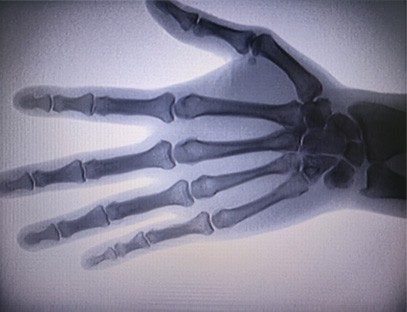

Il-Magni Ortopediċi tar-Raġġi X tagħna huwa prodott ta 'kwalità għolja li kien iddisinjat partikolarment għall-immaġini ortopediċi. Jista 'jintuża għad-dijanjosi u l-ippjanar tat-trattament ta' kundizzjonijiet ortopediċi varji, inklużi ksur, dislokazzjonijiet, artrite u tumuri fl-għadam. Hija mgħammra b'teknoloġija avvanzata tar-raġġi-X li tippermetti immaġini ta 'kwalità għolja b'espożizzjoni mnaqqsa għar-radjazzjoni. Il-magna għandha sistema ta 'immaġni b'riżoluzzjoni għolja u tista' taqbad immaġini ta 'kwalunkwe struttura tal-għadam b'ċarezza kbira.

1. Teknoloġija ta 'l-immaġini avvanzata: il-Magni Ortopediċi tar-raġġi X tagħna tuża teknoloġija avvanzata ta' immaġini biex taqbad immaġini ta 'kwalità għolja ta' għadam u ġogi, u tipprovdi dijanjosi preċiżi u riżultati ta 'trattament imtejba.

3. Wirja ta 'immaġni kbira: Il-magna għandha wirja ta' immaġni kbira, li tipprovdi fluss tax-xogħol effiċjenti u identifikazzjoni faċli ta 'sejbiet kritiċi.